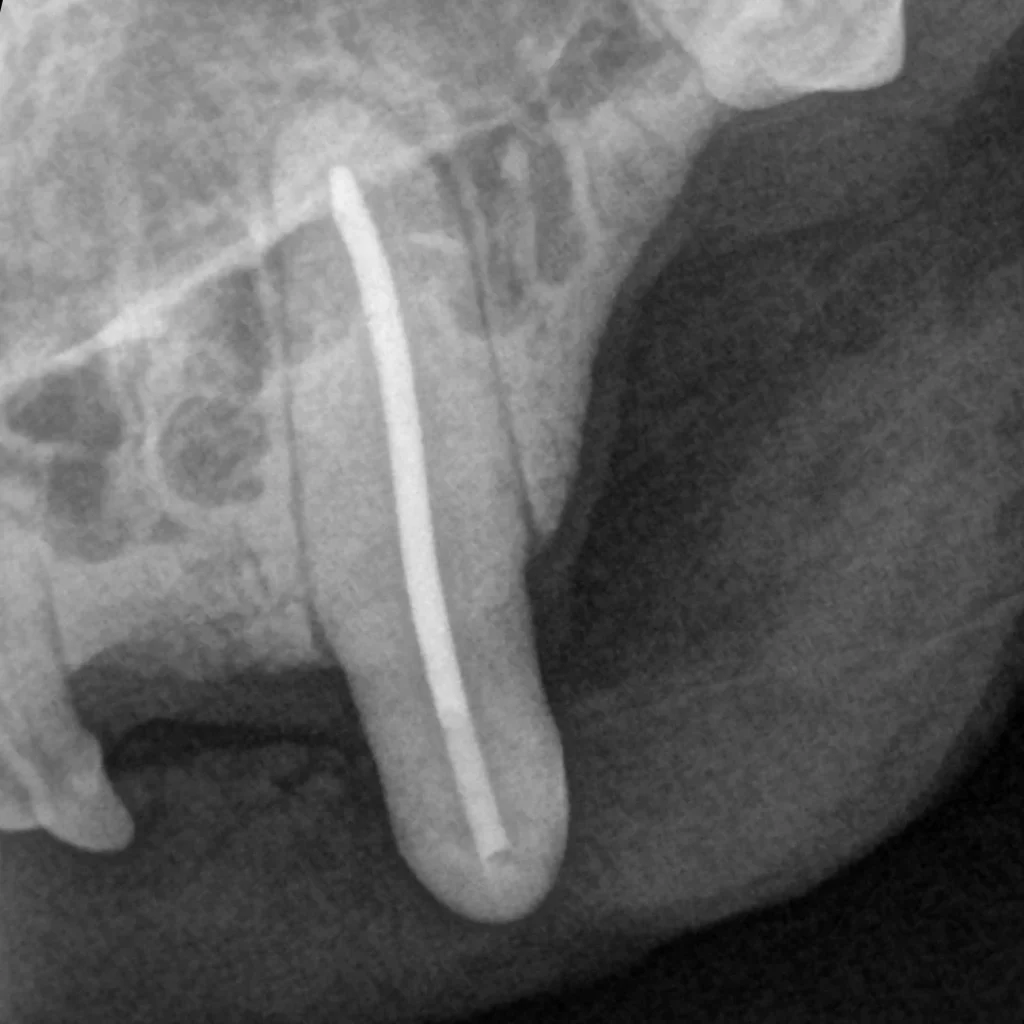

• 육안으로 문제가 없어 보이는 경우에도 치과방사선이나 Cone beam CT 촬영을 통해 치아 흡수성 병변이 확인되는 경우가 많습니다.

치아흡수가 치과방사선에서도 확인됨​

치과방사선으로 확인된 치아흡수